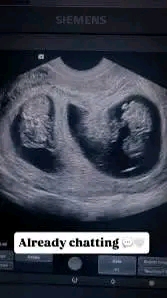

Harvinaiseksi ja sydäntä lämmittäväksi tarkoitetusta kurkistuksesta Kimin ja Minttu Räikkösen yksityismaailmaan on nopeasti tullut yksi fanien puhutuimmista hetkistä. Pari hämmästytti seuraajiaan jakamalla ultraäänikuvia, jotka vahvistivat heidän odottavan kaksosia – iloinen ”kaksoissiunaus”, joka levisi välittömästi sosiaalisessa mediassa. Perheelle, joka tunnetaan yksityiselämänsä tiukasta suojaamisesta, paljastus tuntui epätavallisen avoimelta, lähes symboliselta siitä, kuinka erityinen tämä hetki todella on.